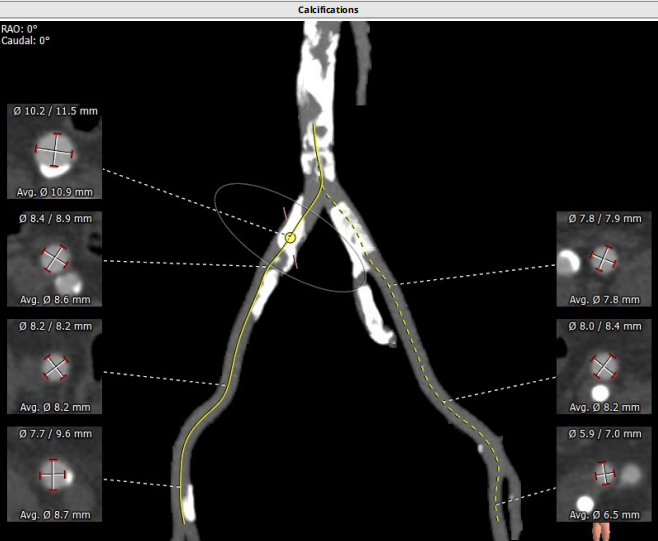

术前CT评估

路入分析:主动脉弓部、胸主动脉、腹主动脉可见多发钙化灶,操作需 谨慎,左颈动脉及左锁骨下动脉直径符合入路条件。

患者TYPE2型二叶瓣,左无、右无冠窦融合可能,左右部分粘连可能,轻度钙化,瓣叶增厚,法式窦结构不大,双冠高度可,升主动脉未见明显增宽,心脏角度不大,左室大,主动脉弓部走行较平缓,主动脉弓部、胸主动脉、腹主动脉可见多发钙化灶,操作需 谨慎。

患者主动脉根部结构复杂,极重度钙化,腹主动脉及双侧髂总动脉存在环形钙化。常规股动脉直径入路困难,吴延庆教授组织团队在术前制定完成手术预案,根据病人情况选择采用All IN ONE技术通过右侧股动脉途径入路进行手术。术中未使用起搏器,通过超硬导丝诱发室颤来降低血压心率的方法,配合调整ECMO转速来完成球囊预扩与VenusA L26瓣膜释放置换。释放完毕后出现心室颤动,予以电除颤后,心脏停搏,胸外按压三十秒恢复自主心率,造影观察后有少量反流,测得压差9mmhg,手术效果完美,瓣膜置入位置良好、形态完整。